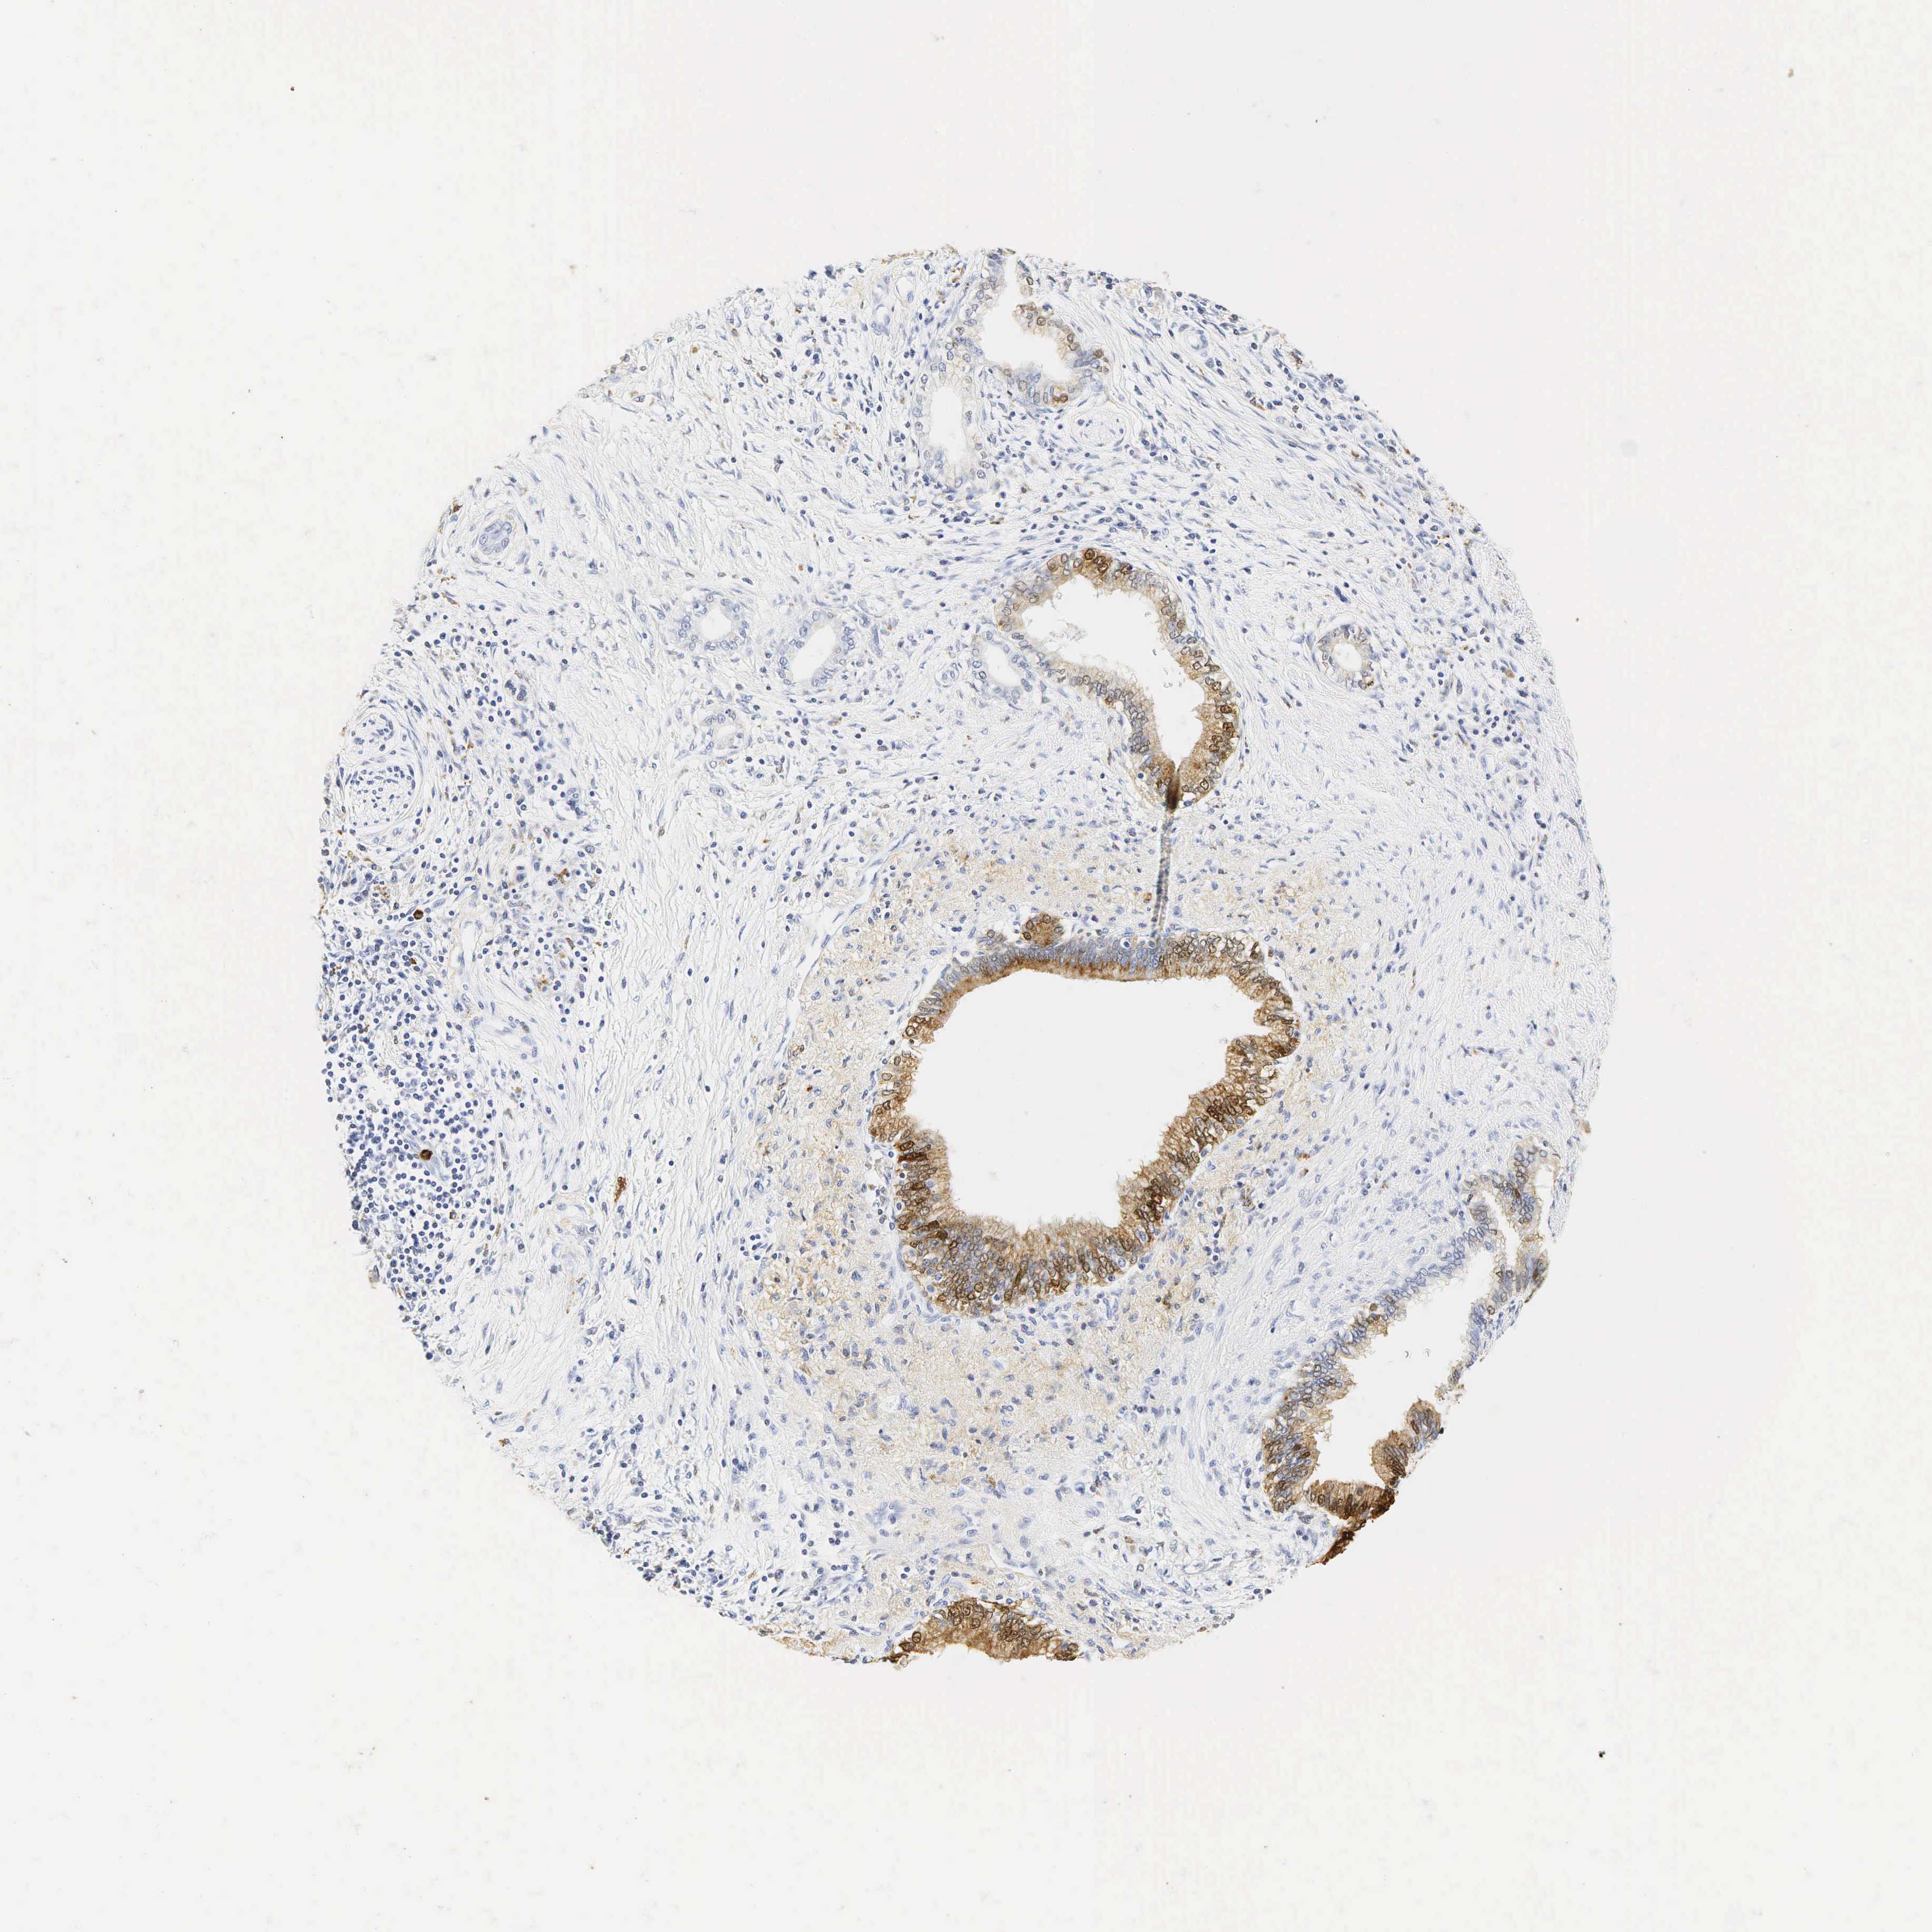

PANCREATIC CANCER - Protein expressioni

A mouse-over function shows sample information and annotation data. Click on an image to view it in a full screen mode. Samples can be filtered based on level of antibody staining by selecting one or several of the following categories: high, medium, low and not detected. The assay and annotation is described here.

Note that samples used for immunohistochemistry by the Human Protein Atlas do not correspond to samples in the TCGA dataset.

Antibody stainingi

Antibody staining in the annotated cell types in the current human tissue is reported as not detected, low, medium, or high, based on conventional immunohistochemistry profiling in selected tissues. This score is based on the combination of the staining intensity and fraction of stained cells.

Each image is clickable and will lead to virtual microscopy that enables deeper exploration of all samples and also displays staining intensity scores, fraction scores and subcellular localization as well as patient and tissue information for each sample.

Antibody HPA048284

Antibody CAB000055

Adenocarcinoma, NOS